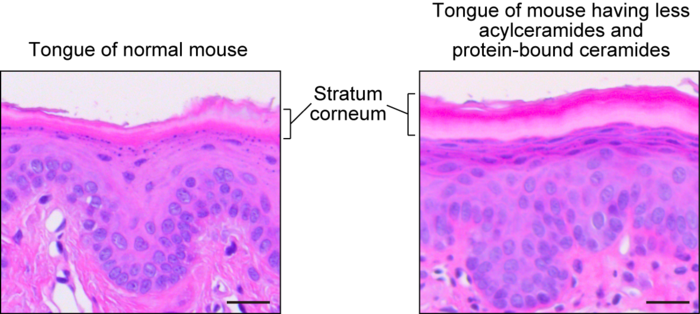

The tongues of mice having less acylceramides and protein-bound ceramides exhibited hyperkeratosis, the thickening of the outermost layer, often observed in the skin with barrier deficiency, and the mice were significantly more sensitive to capsaicin in drinking water, indicating that the oral barrier formation was affected.